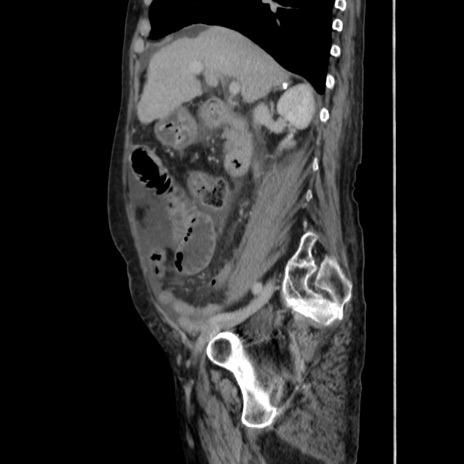

症例31(矢状断像)

【症例】80歳代 女性

【主訴】腹部膨満感

【現病歴】他院にて肝硬変にてフォロー中。1週間前から便秘、腹部膨満感、臍部腫瘤あり受診となる。

【既往歴】肝硬変

【身体所見】腹部膨隆あり、皮膚変化なし、疼痛なし。

【データ】WBC 4600、CRP 0.25